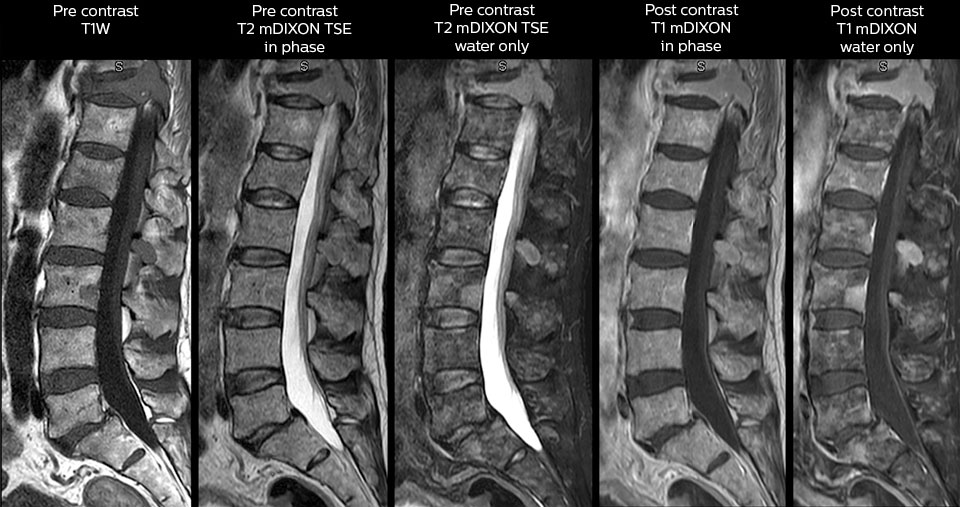

„Mit mDIXON TSE-Sequenzen ist es dank der T2-gewichteten Bilder auf Wasserbasis aus derselben Erfassung möglich, gleichzeitig morphologische Veränderungen aus den T2-gewichteten In-Phase-Bildern zu charakterisieren und ödematöse Veränderungen darzustellen. Auf diese Weise können anatomische und morphologische Befunde wie eine partielle oder komplette Bandruptur, ein knöcherner Ausriss oder ein Hämatom abgeklärt werden.“ „In Bezug auf die Beurteilung von Weichteilgewebe bietet mDIXON ähnliche Vorteile. Bei einer T2-gewichteten mDIXON TSE-Erfassung helfen die multiplen Kontraste zum Beispiel bei der Abklärung von pathologischen Befunden in Faserbündeln der peripheren Nerven, die auf anatomischen oder entzündlichen Veränderungen beruhen können.“ „Bei peripheren Gelenken erhalten wir mit mDIXON TSE eine gute Qualität in diffizilen Bereichen. Bilder mit Fettsuppression erscheinen vollständig homogen, auch bei einer großen Abdeckung mit 3,0 T – zum Beispiel beim Schulter- oder Beckengürtel – bzw. in den Gelenkflächen oder um Metallprothesen herum*, wo eine Fettsuppression mit STIR oder spektraler Suppression häufig unzureichend ist und zu Schwierigkeiten bei der Diagnose führt. Wenn ein diagnostisches Bild auf Anhieb richtig dargestellt wird, ist es nicht nötig, eine Sequenz zu wiederholen oder hinzuzufügen.“ „Mit mDIXON TSE-Sequenzen ist es dank der T2-gewichteten Bilder auf Wasserbasis aus derselben Erfassung möglich, gleichzeitig morphologische Veränderungen aus den T2-gewichteten In-Phase-Bildern zu charakterisieren und ödematöse Veränderungen darzustellen. Auf diese Weise können anatomische und morphologische Befunde wie eine partielle oder komplette Bandruptur, ein knöcherner Ausriss oder ein Hämatom abgeklärt werden.“ „In Bezug auf die Beurteilung von Weichteilgewebe bietet mDIXON ähnliche Vorteile. Bei einer T2-gewichteten mDIXON TSE-Erfassung helfen die multiplen Kontraste zum Beispiel bei der Abklärung von pathologischen Befunden in Faserbündeln der peripheren Nerven, die auf anatomischen oder entzündlichen Veränderungen beruhen können.“

„mDIXON TSE wird in unserer Notaufnahme ausgiebig für die Wirbelsäulenbildgebung eingesetzt“, führt Dr. Karis aus. „Besonders vorteilhaft ist, dass dieses Verfahren im Hinblick auf suszeptibilitätsbezogene Probleme sehr stabil ist, die häufig bei klassischen spektralen, fettgesättigten Bildern auftreten. Im Wesentlichen treten derartige Probleme beim mDIXON-Verfahren überhaupt nicht auf. Wir sind wirklich froh, in unserer Notaufnahme über die fettfreie Bildgebung des mDIXON-Verfahrens zu verfügen.“

„Für die routinemäßige, kontrastmittelfreie Untersuchung der Brust- und Halswirbelsäule führen wir zum Beispiel eine mDIXON T2-TSE-Sequenz durch, die uns zwei Ergebnisse liefert: die T2-gewichteten Bilder auf Fett- und Wasserbasis sowie die sagittalen T2-gewichteten Bilder auf reiner Wasserbasis. Anschließend erfolgt noch eine axiale Gradientenecho-Untersuchung.“

Routineuntersuchung der Halswirbelsäule

Dieser Patient wurde mit Kopfschmerzen vorstellig, die sich bei einer Flexion des Nackens verschlimmerten, und wir sehen hier eine Chiari-Malformation vom Typ I mit niedrig liegenden Kleinhirntonsillen sowie degenerativen zervikalen, thrombolytischen Veränderungen.